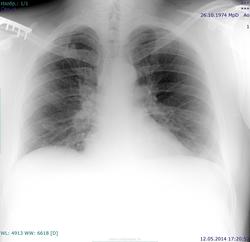

Пациент 1974 г.р., кашель, повышение температуры. Увеличение бронхопульмональных ЛУ справа. Можно ли, предполагая, что гиперплазия ЛУ может быть вызвана вирусной инфекцией (например, инфекционный мононуклеоз) назначить контроль или желательна конс фтизиатра? Архива нет. Изменинения 1 р справа - посттравматические?

Охота вам так голову ломать с инфекционным мононуклеозом. Пишите "р-признаки лимфоаденопатии", к "конс фтизиатра" можете добавить "конс. онколога" и успокоиться. Р-контроль вряд ли будет информативен.

И отчего лимфоаденопатия односторонняя?.. Либо - с обеих сторон, либо... - очередной поворот!))

Досняли. Первый снимок был с неполным вдохом. Уже собиралась отправлять в ПТД.

Нет. Мне непонятно, как дифференцировать расширение корней за счет сосудов и лу. По боковому не всегда получается. Если я всех с подозрением на лимфаденопатию буду переснимать нарушится работа кабинета.

Т.е. по первому снимку сразу можно было сказать, что это сосуды?

Пожалуйста, скажите, по каким признакам. Только по неполному вдоху и одностороннему поражению?

[/quote] Здесь нет одностороннего поражения. А на полноту вдоха-выдоха ( смотрите- на каком уровне купол диафрагмы) всегда обращайте внимание и небольшой разворот, особенно у детей- сразу " вылечите" от многих болезней![/quote] ++